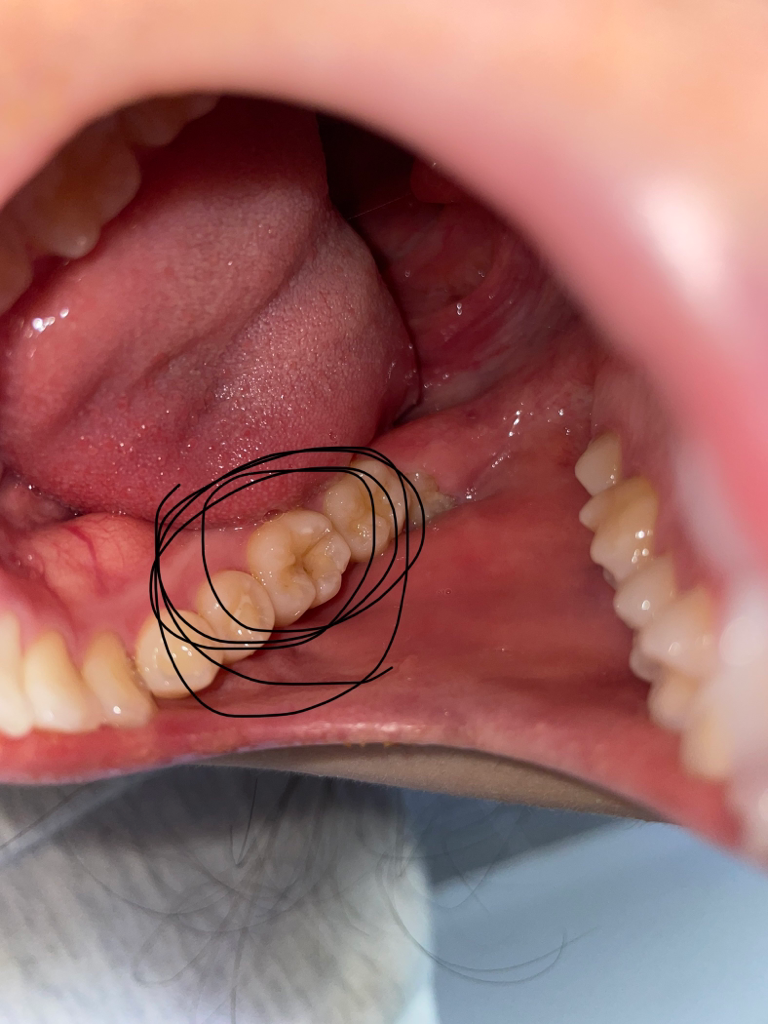

사진 상으로는 충치가 있어 보이나 깊이 등을 판단하기 위해서는 임상 사진만으로는 힘듭니다. 충치는 겉으로 보기에는 얼마 없어 보여도 삼각형 형태로 충치가 밑으로 확산되기 때문에 더 심할 수 있습니다. 치과 방문 후 방사선 사진 등을 통해 판단해볼 필요가 있습니다. 충치는 단기간에 크게 진행되지 않으니 목요일 날 치과 방문 후 치료하시길 바랍니다.

많이 심해보이지는 않지만 간혹 보기보다 충치가 더 많이 진행된 경우도 종종 있습니다.

충치는 있으실꺼 같긴합니다. 하지만 저기 구멍뚤린건 원래 치아 모양이 그렇게 생긴거에요. 충치 깊이는 엑스레이 사진등을 찍어보시고 판단해야되니 치과에 가셔서 검진을 받아보세요.

충치부위가 작아보이고